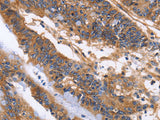

Applications WB,  IHC

IHC 1:50-1:200